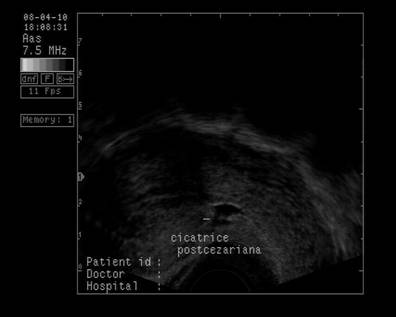

Fig. Nr 335 Lohiometrie in ziua a XXIII a postoperatie cezariana

Fig. Nr. 336 Pacienta la peste un an dupa a doua operatie cezariana, ecografie vaginala, cu linie imaginea anecogena indusa de cicatricea peretelui anterior istmic uterin